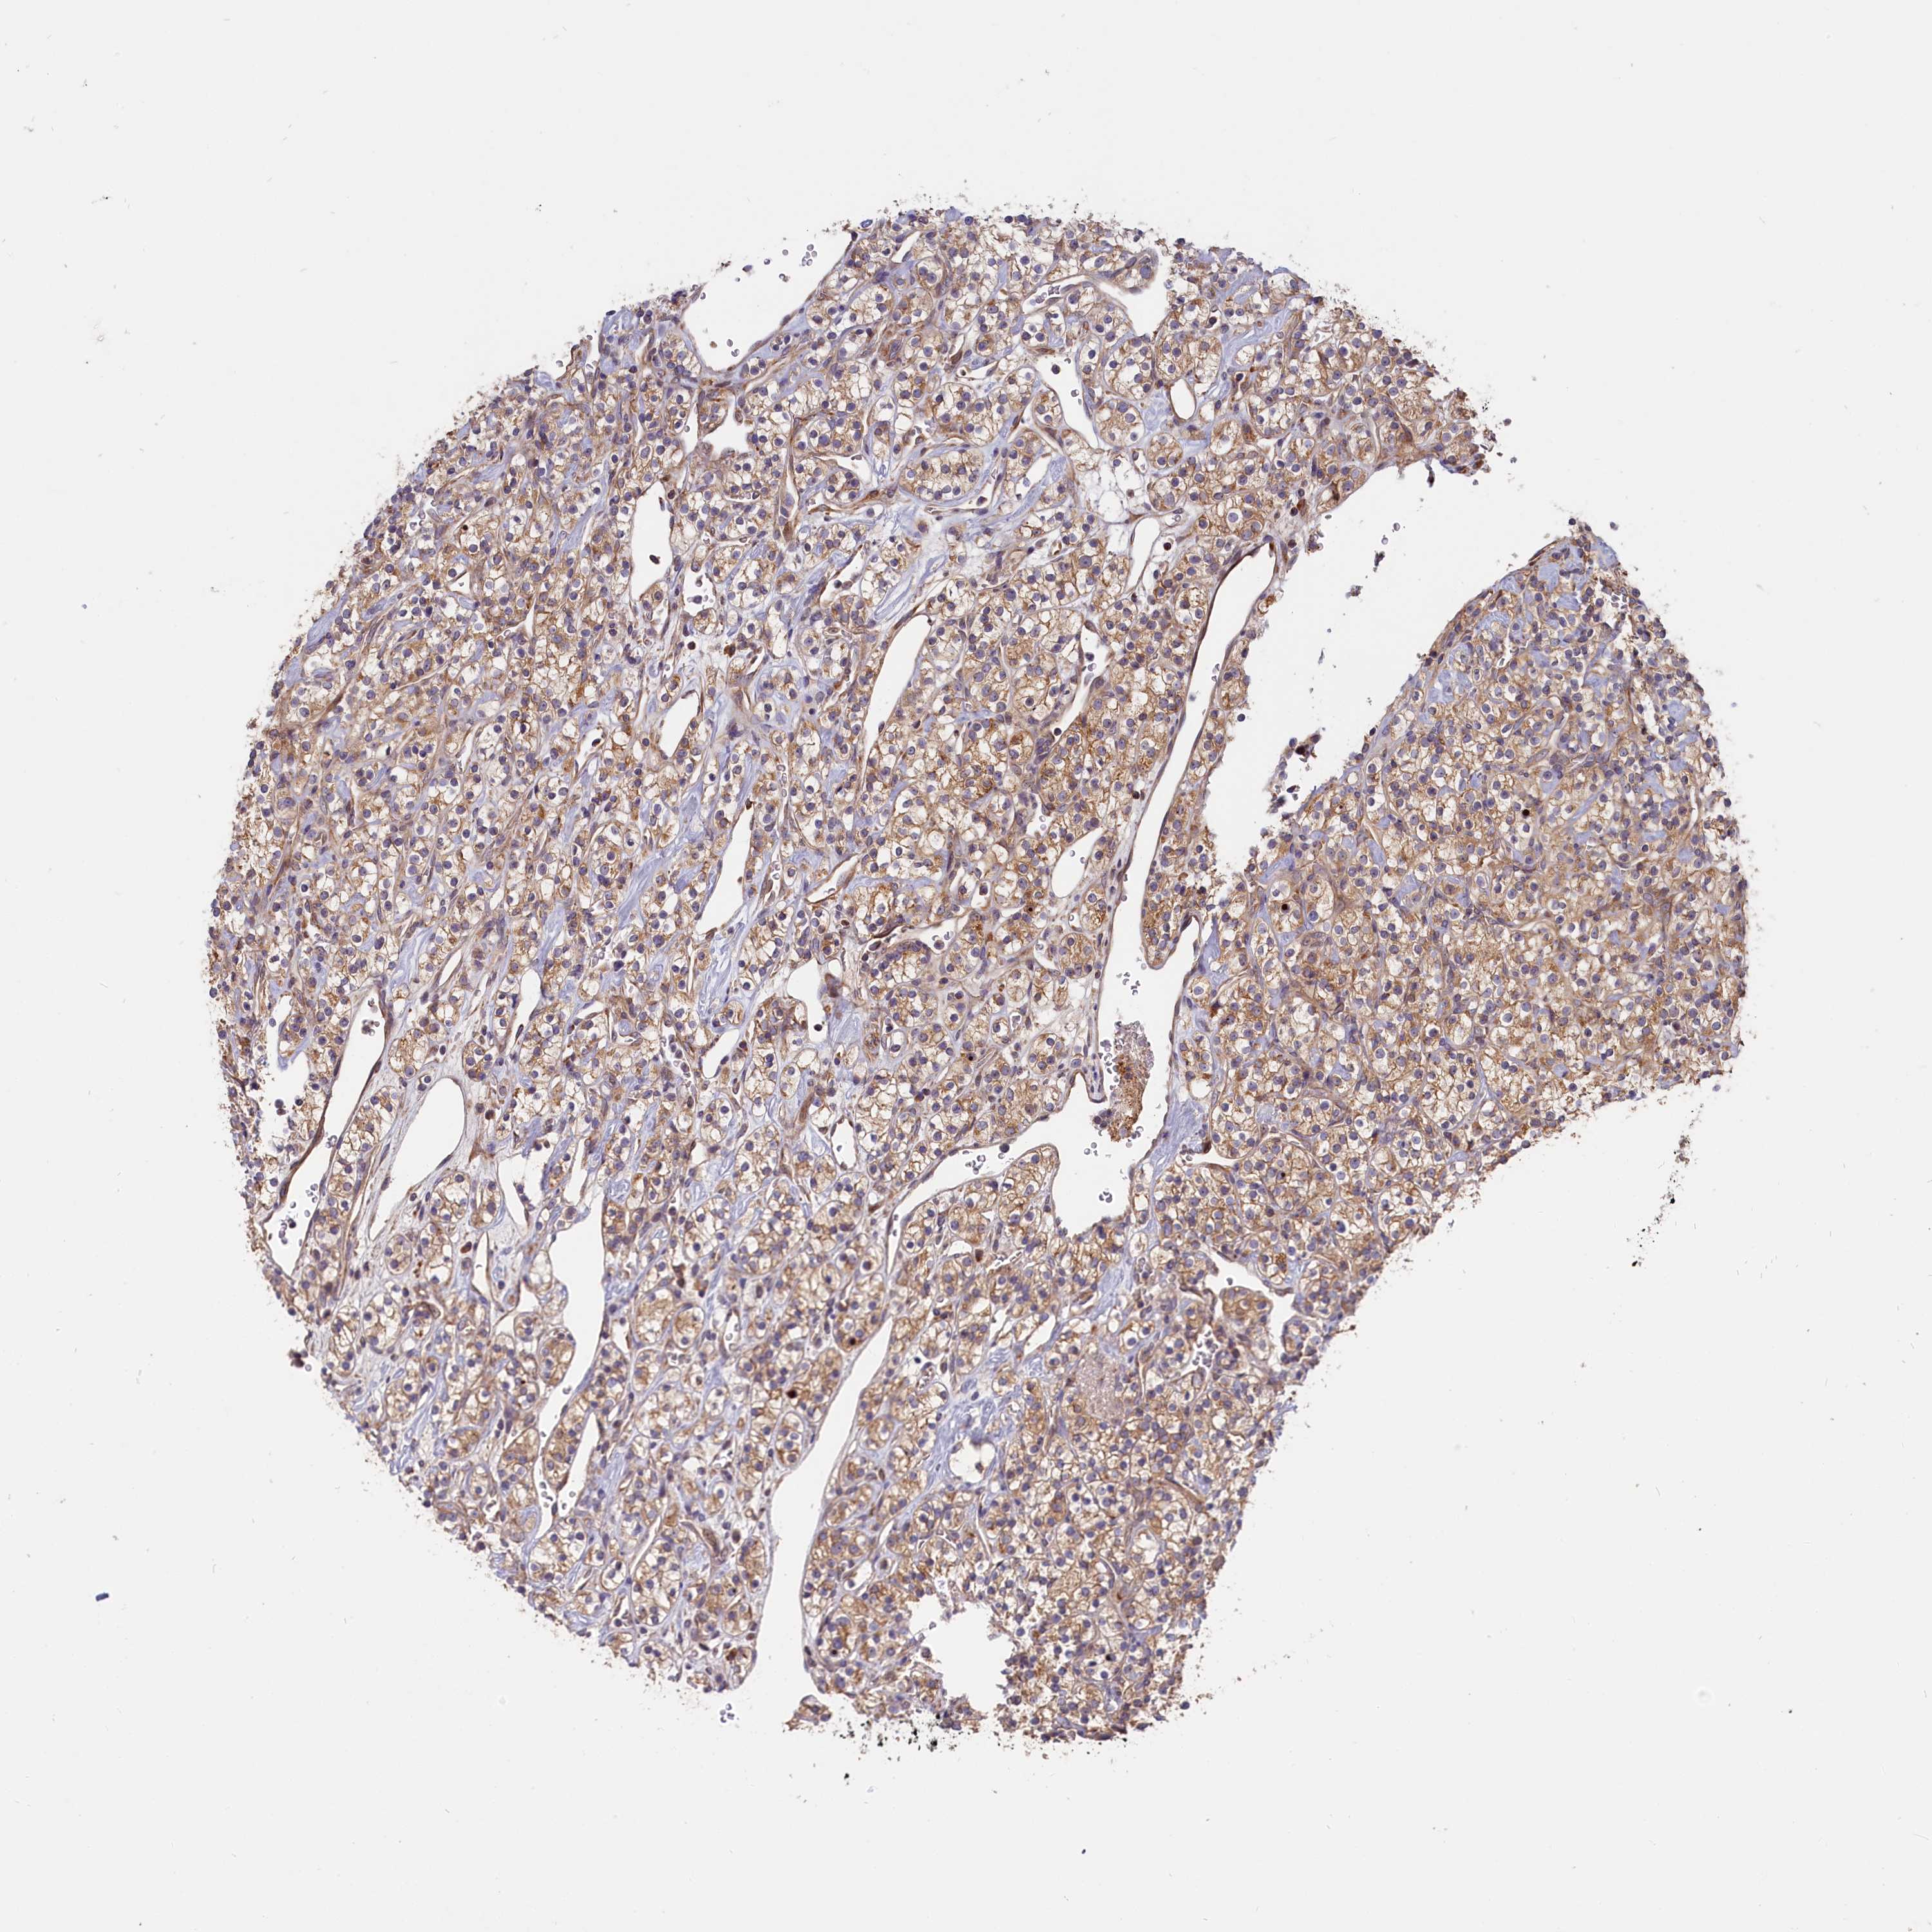

CANCER RENAL CANCER Show tissue menu

KICH TCGA KIRC TCGA KIRC VALIDATION KIRP TCGA PROTEIN RCC CPTAC PROTEIN EXPRESSION